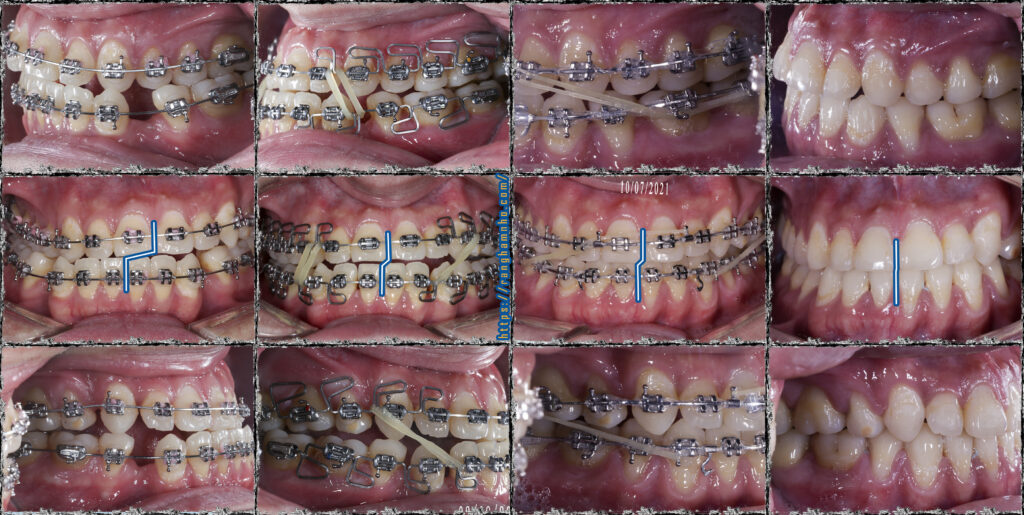

Tình hình khi gặp gỡ: còn nhiều khoảng nhổ răng, khớp cắn ngược răng cửa, cắn chéo nhóm răng hàm cung 1. Đường giữa hàm dưới lệch nguyên 1 răng cửa. Mặt thẳng lệch rất rõ, cằm đưa hẳn sang bên phải.

Xử lí: Đóng khoảng hàm dưới đến mức vừa phải để giải quyết cắn ngược răng cửa. Bẻ MEAW trên TMA 17×25 định vị lại vị trí xương hàm dưới. Sau đó chuyển lại kĩ thuật dây thẳng để kết thúc sau gần 2 năm.

Kết quả: đường giữa gần như thẳng, xương hàm dưới định vị về vị trí bình thường. Khuôn mặt cải thiện khá so với trước điều trị nhưng không thể hoàn hảo do căn nguyên sai lệch kết hợp đến từ sai lệch xương ![]()